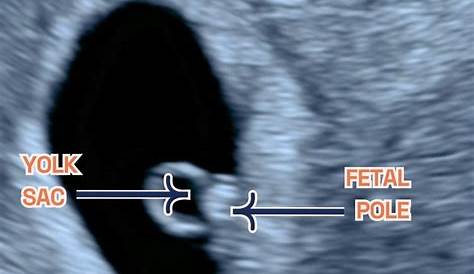

Что делать, если на 6 неделе нет плодного столба?

Сегодня я прошла раннее сканирование, и мы увидели желточный мешок, но не фетальный полюс. Поле плода не определено. Моя обьект не мог видеть фетальный полюс и очень обеспокоен. По-видимому, был только мешок и нет полюса плода.

Да, в 6 недель у меня был желточный мешок, но не было фетального столба.

Поздравляю вашего ребенка, я молюсь, чтобы вы сделали это до полного срока и иметь безопасные роды. Полюс плода — это утолщение в области эмбриона. 6 недель — это своего рода серая область для полюса плода и сердцебиения. Они могли видеть гестационный мешок и желточный мешок, но никакого полюса плода.

Нет ли у плода шеста на 6 неделе?